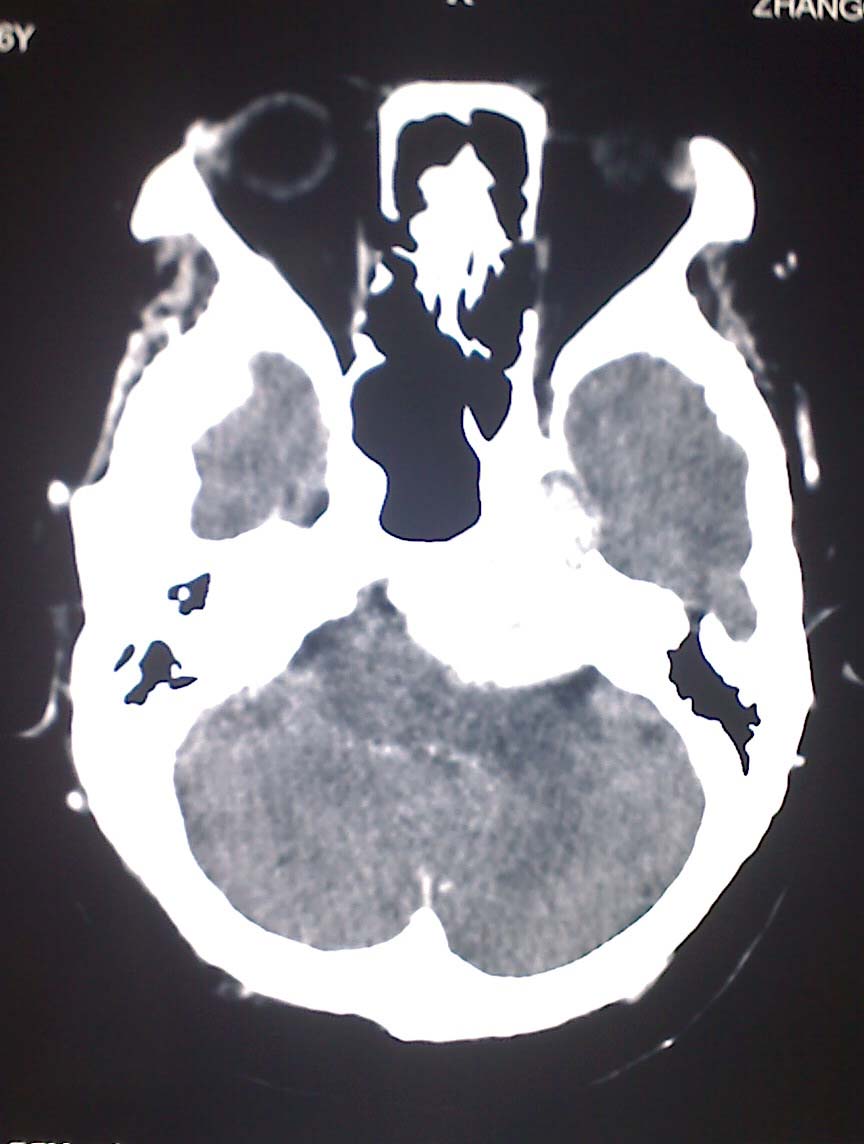

女性,56岁,查体所见,请会诊

平扫为较高密度,增强后病灶明显强化,边界清楚水肿不明显.考虑脑膜瘤.

左岩骨尖区脑膜瘤

从病变位置和强化表现看倾向脑膜瘤,但其跨越中后颅窝,也要结合临床,不能忽略三叉神经瘤,不过后者囊变较多。此病例的不足是无骨窗对照,脑膜瘤比较容易出现临近骨骼的异常。

左岩骨尖区占位病变,平扫呈高密度,病变跨中后颅窝生长,岩骨可见骨质吸收,周围未见明显水肿,增强扫描病灶明显强化。考虑左岩骨尖区脑膜瘤。

此片最大的缺憾是没骨窗,钙化及颅骨的改变不好看